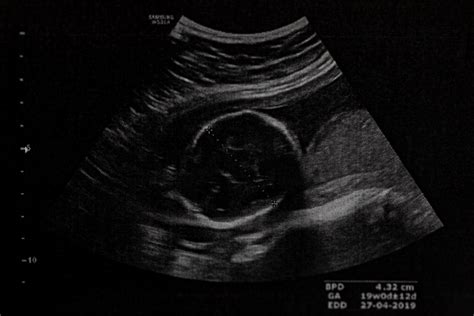

Bábätko sa v maternici ku koncu tehotenstva väčšinou umiestňuje hlavou nadol, pretože je to najlepšia pozícia na nadchádzajúci pôrod. Táto poloha, známa ako cefalická poloha, je považovaná za optimálnu pre prirodzený vaginálny pôrod. Väčšina bábätiek sa začína otáčať do tejto polohy medzi 32. a 36. týždňom tehotenstva, ale tento proces je individuálny. Niektoré bábätká môžu zaujať túto polohu už okolo 28. týždňa, najmä u prvorodičiek. Po 36. týždni tehotenstva, vzhľadom na rastúcu veľkosť dieťaťa a obmedzený priestor v maternici, už zvyčajne nedochádza k významným zmenám polohy.

Fyziologické polohy bábätka sú tie, pri ktorých je os maternice a bábätka v jednej línii. V týchto polohách nie je dieťa v žiadnom neprirodzenom uhle a jeho os sa s maternicou nekrižuje. Pozdĺžna poloha hlavičkou je ideálna pôrodná poloha, ktorá nebráni vaginálnemu pôrodu, pretože dieťa je v nej otočené hlavičkou nadol. V rámci tejto polohy ešte rozlišujeme predné a zadné postavenie. Predné postavenie v pozdĺžnej polohe hlavičkou je najideálnejšou pôrodnou polohou, v ktorej je bábätko hlavičkou pri panvovom vchode a tvárou k chrbtu matky. Toto postavenie umožňuje dieťaťu prejsť pôrodnými cestami bez väčších problémov.

Obrátená poloha, teda situácia, keď dieťa nie je otočené hlavičkou nadol, sa môže stať nočnou morou posledného trimestra. Niektoré deti sa s touto konečnou "piruetou" neponáhľajú a iné sa dokonca do najpriaznivejšej pozície na pôrod ani neotočia. Príčiny neotočenia dieťaťa nie sú vždy jednoznačné. Zhruba v 5% tehotenstiev plod ostane v menej obvyklej polohe, najčastejšie koncom panvovým, teda hlavičkou nahor a zadočkom nadol. Niekedy sa môže rodiť aj v tejto neštandardnej polohe, no prináša to so sebou viaceré riziká, najmä u chlapcov. V takýchto prípadoch lekári zvyčajne uvažujú nad cisárskym rezom a matka naň má v takom prípade automaticky nárok.

Pôrod koncom panvovým znamená, že dieťatko je k pôrodným cestám otočené zadočkom alebo nožičkami. V maternici môže pripomínať malého budhu. Táto poloha už predstavuje komplikáciu a pôrod koncom panvovým je rizikom, preto vo väčšine prípadov lekári pristupujú k cisárskemu rezu. Cisársky rez je z hľadiska bezpečnosti často považovaný za lepší variant ako klasický pôrod koncom panvovým, kde je väčšie riziko komplikácií. Samozrejme, existujú aj prípady, kedy pôrod koncom panvovým prebehol prirodzene a bez komplikácií.